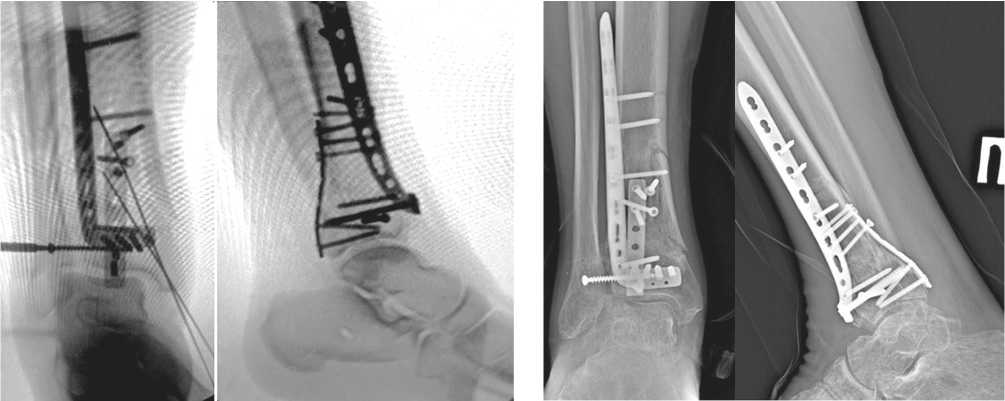

На основании полученных данных выбрали хирургические доступы: заднемедиальный и передне-латеральный. Осуществлён остеосинтез из этих доступов с установкой передне-латеральной пластины и 1/3 трубчатой пластины сзади (рис. 4). Задне-медиальный доступ позволил полностью визуализировать перелом заднего края ББК, осуществить репозицию отломков ad occulus и уложить ранее пре-моделированную при помощи 3D-прототипа 1/3 трубчатую пластину. Далее пациента перевернули на спину, выполнили передне-латеральный доступ. Метадиафизарный компонент перелома фиксировали передне-латеральной премоделированной L-образной пластиной, передне-латеральный фрагмент (Chaput) — винтом. Применённый доступ позволил визуализировать передней край вырезки малоберцовой кости для прецизионной репозиции фрагмента Chaput.

По шкале AOFAS AHS сумма баллов составила 82 балла, по шкале VAS-FA — 41 балл, в обоих случаях сумма баллов соответствовала отличным результатам. При оценке рентгенограмм (рис. 5) по критериям mRUST получено 13 баллов, что соответствует перелому в стадии консолидации. Миграции фиксаторов, вторичного смещения не выявлено.

Рис. 4. Интраоперационные рентгенограммы пациента в прямой и боковой проекциях

Рис. 5. Рентгенограммы через шесть месяцев после операции